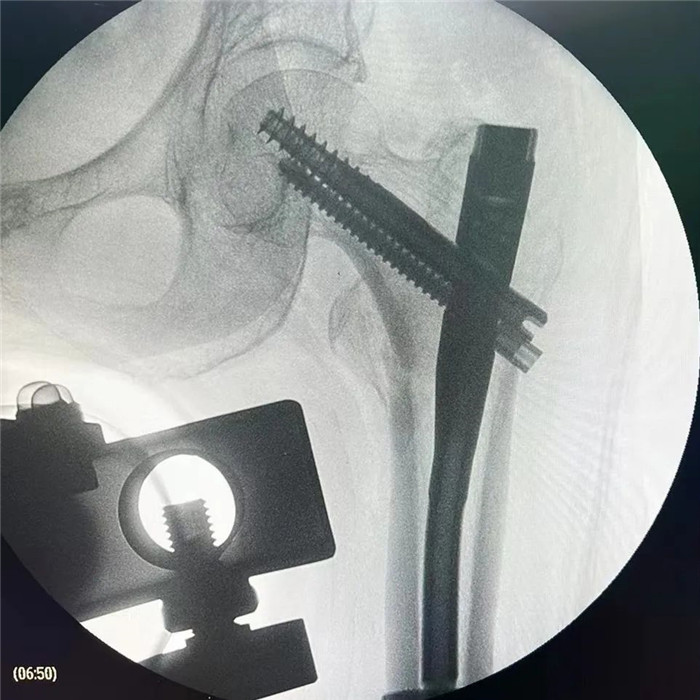

在手術(shù)團(tuán)隊(duì)及患者家屬的大力支持下,羅軍主任團(tuán)隊(duì)為洪阿婆實(shí)施了閉合復(fù)位INTERTAN內(nèi)固定術(shù)。雖然手術(shù)風(fēng)險(xiǎn)較大,但憑借精湛的技術(shù)及豐富的臨床經(jīng)驗(yàn),手術(shù)十分成功而且僅僅用了1個(gè)小時(shí),術(shù)中出血不多,術(shù)后患者恢復(fù)得很好,第二天就可以在起床活動(dòng),極大的提高了患者的生活質(zhì)量,避免了長期臥床造成的并發(fā)癥。

目前我院骨科對(duì)于高齡老年人股骨頸骨折行人工髖關(guān)節(jié)置換手術(shù)技術(shù)已經(jīng)非常成熟,術(shù)后2~3天就可以下地活動(dòng),可以明顯提高高齡老人的生活質(zhì)量,效果良好。